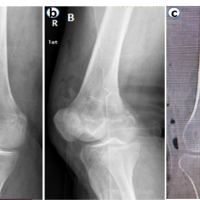

This retrospective analysis was conducted in a tertiary health-care facility from January 1, 2023, to November 30, 2023. The study examined combined distal femur plating and retrograde femur nailing results in patients with comminuted distal femur fractures with AO classifications of 33A3, 33C2, and 33C3. Pre-operative X-rays AP and lateral were taken with computed tomography scan as shown in 1a-c Figs., respectively. Patient data were extracted from medical records and analyzed in Excel spreadsheets. No patient identification was gathered to protect anonymity, as per ethical norms. The study comprised a review of Lysholm scores, Visual Analogue Scale (VAS) scores for pain at 6 months after surgery, and knee range of motion (ROM) measures at 6 weeks, 3 months, and 6 months after surgery as primary end metrics.